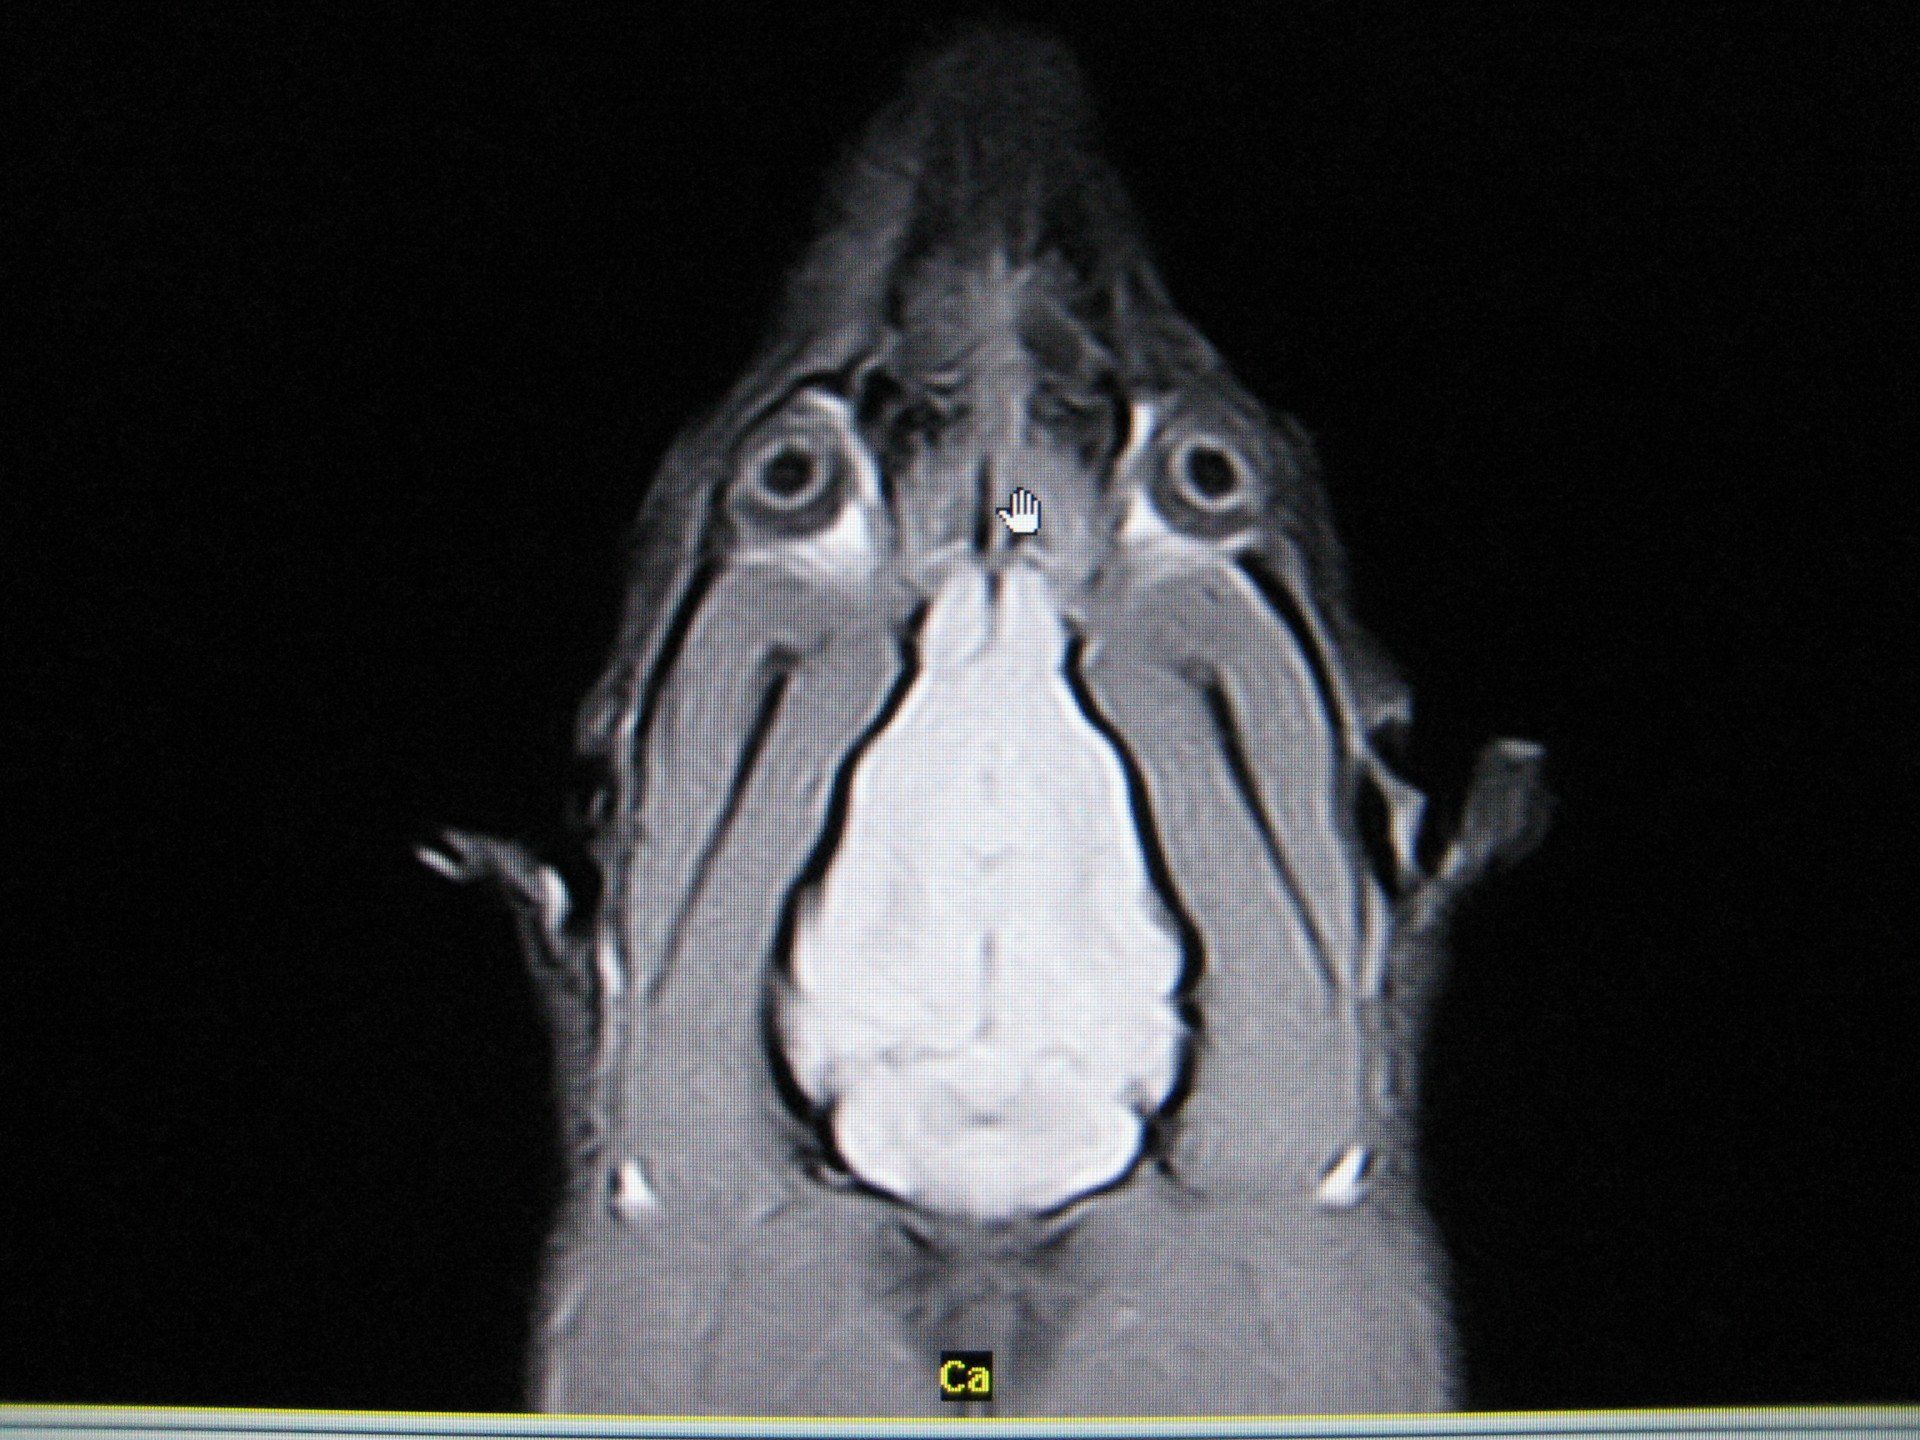

Notre plateau technique permet de réaliser tous les examens complémentaires de la médecine conventionnelle pour tous les patients : radiographie, échographie, endoscopie, scanner et IRM.